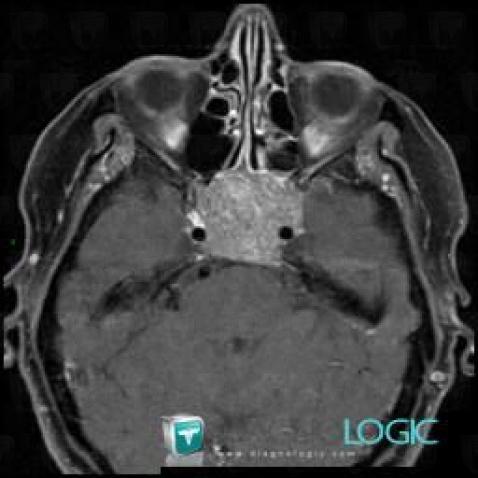

Macroadénome hypophysaire, Hypophyse et région parasellaire, IRM

Voici les informations spécifiques à l'image clé ci dessus:

- Diagnostic Macroadénome hypophysaire, Localisation(s) Hypophyse et région parasellaire, comportant les gammes Lésion en hypersignal T2 sellaire ou parasellaire